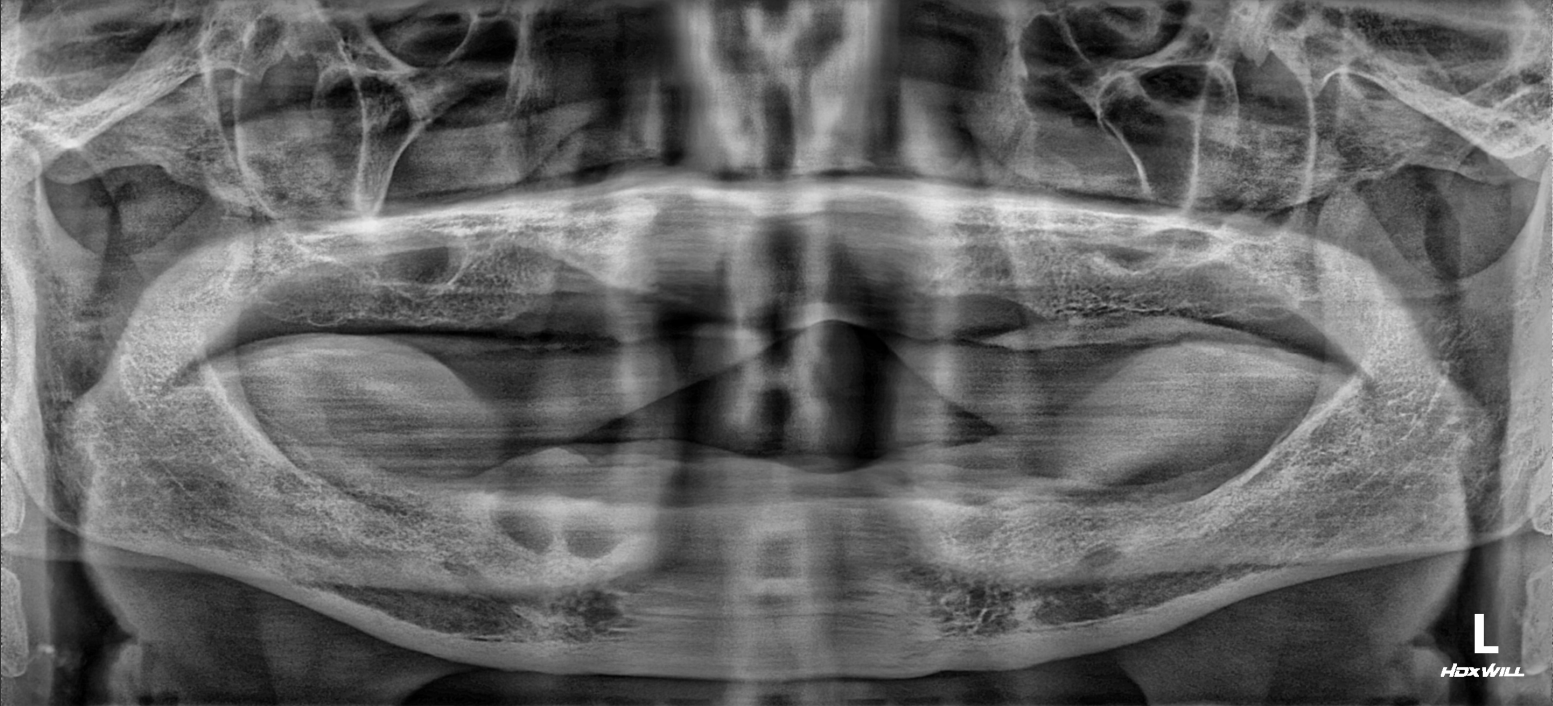

OPG - BEFORE